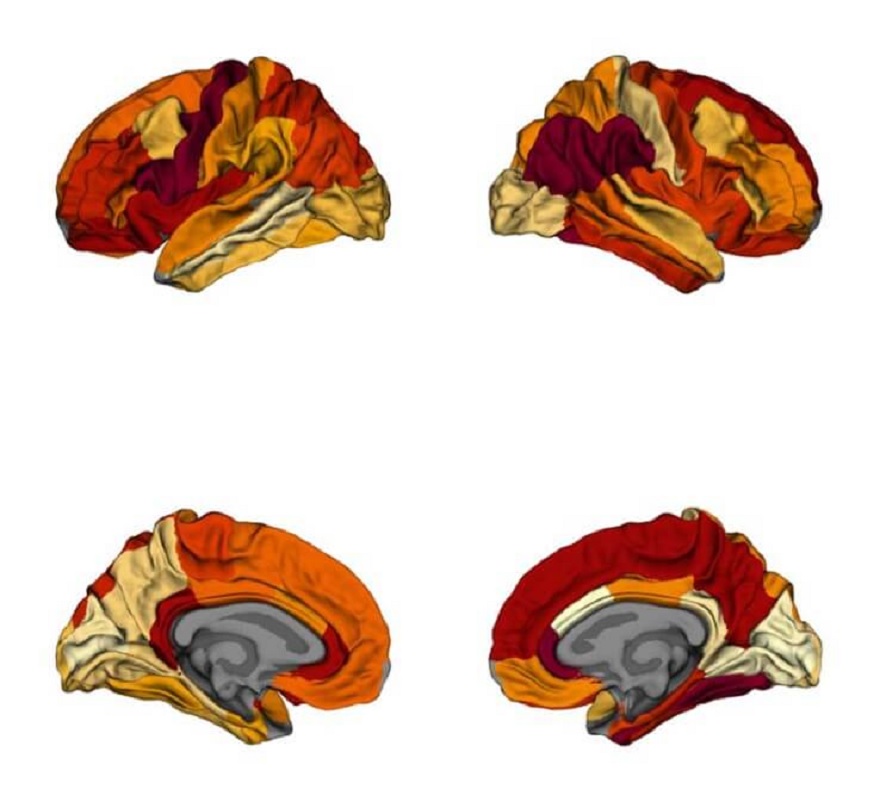

sağ parietal temporal kortekste ve sol prefrontal kortekste beyinAşırı kiloluluk ve Alzheimer hastalığının gri maddenin küçülmesine niçin olduğu ortaya çıkarıldı. Bundan dolayı araştırmacılar, zayıf olmanın bilişsel gerilemeyi yavaşlatabileceğini ve bunama riskini azaltabileceğini iddia ediyor. Montreal Nöroloji Enstitüsü Hastanesi’ndeki McGill Üniversitesi araştırmacılarına bakılırsa, aşırı kiloluluk ve Alzheimer hastalığı (AD) aynı tip nörodejenerasyona yol açabilir.

Aşırı kiloluluk ve Alzheimer hastalığı daha ilkin bağlantılı olmasına karşın, bu, Alzheimer hastalığı ve obezitede beyin küçülme modellerini direkt karşılaştıran ilk çalışmadır. Alzheimer hastalığına benzer şekilde, aşırı kiloluluk, beyin dejenerasyonuna yol açan amiloid birikimi ve beyindeki kan akışını etkileyen serebrovasküler bozukluk ile ilişkilidir.

Araştırmacılar, Alzheimer hastalarında, sıhhatli bir denetim grubunda ve obez ve obez olmayan deneklerde gri madde büzülmesini haritaladılar. Gri cevher atrofisi için ortalama 1.300 şahıs örneklendi ve neticeleri obez ve Alzheimer hastalarının sonuçlarıyla karşılaştırıldı.